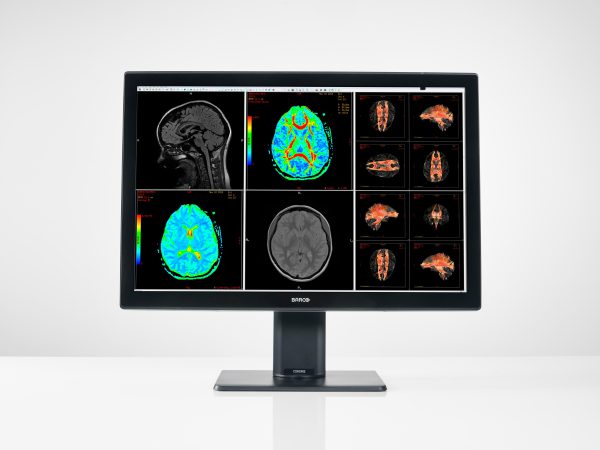

4メガピクセルモニターは、現在ほとんどのメーカーが製造を辞めているため、4メガユーザーが機種を変えようと思うと2メガモニター2台で対応しなければならない。コスト面でもスペース面でもデメリットが大きいが、そんなユーザーに選ばれているのが、このCoronis Fusion 4MPである。

ワイドスクリーンによる1面モニターによって、1台でCT、MRI、超音波などの画像を同時に並べて比較検証ができる。また、世界のバルコが誇る新技術であるWideGamutと、独自のカラー画像技術であるSteadyColor™、GSDFモノクロ表示によって、4メガとは思えないほど広域なカラー画像表示を可能にした。高画質な画像と表示環境を提供することで、画像観察の質と効率が大幅に向上する。

さらに低消費電力や省スペース化などによってコスト面でも医療現場を支援するほか、他には類を見ない最長5年間4万時間の輝度保証が付くなど、導入後のサポートも充実している。

Coronis Fusion 4MP

「Coronis Fusion 4MP」は、従来よりも広い色域でのカラー表示を可能にしたPACS向けカラーディスプレイ。モノクロ表示(GSDF)とリニアカラー表示を両立し、ビューア毎に輝度変更可能。キャリブレーション推奨輝度600cd/㎡を40,000時間保証する高輝度表示・ロングライフ設計。

Coronis Fusion 4MP(MDCC-4430)